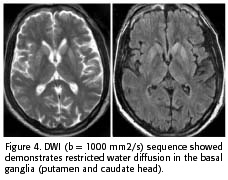

The MRI was performed at the presentation and revealed hyperintensity of the basal ganglia on T2W, FLAIR and DWI sequences. The T1W sequence showed a slight hypointensity of the basal ganglia and no contrast enhancement (Figure 3 and 4). The ADC was 0,44 x 10-3 mm2/s in the putamen and 0,41 x 10-3 mm2/s in the caudate head, confirming restriction of water diffusion (5). Basic biochemical and serological exams were performed and were negative.

Moreover, both patients showed signal changes on T2W and FLAIR in the putamen and caudate nuclei early in the course of the disease (2 to 4 months after first symptoms). In addition, the DWI sequence demonstrated restriction of the water motion in the striatum. The striatal hyperintensity could be seen early in the evolution of sCJD and supported the clinical diagnosis (2, 5-7, 9). The DWI is the most specific for the diagnosis of sCJD (2). Many diseases could manifest with basal ganglia hyperintensity on T2W, DWI and FLAIR images (ischemic, edematous, metabolic and toxic lesions, inborn errors of metabolism, Leigh's disease and mitochondrial encephalomyopathies in general), but these findings are transitory and observed in the acute phases of these diseases only (9). The persistence of the DWI hyperintensity images associated with typical clinical signs greatly suggests sCJD (2). Although, there are few reports about late phase of sCJD and we do not know for how long the restriction of water motion could be noted on the DWI.

The origin of the basal ganglia diffusion abnormality in the sCJD is not well-known to date. Some authors have suggested that the vacuolar accumulation in the cellular cytoplasm could explain the restriction of the water motion on DWI (5, 6).